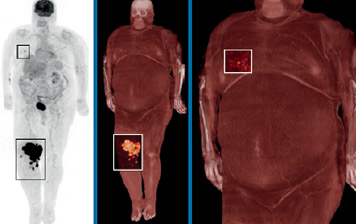

TOF reconstruction using SSS with tail-fitting (left image in each pair) and ×Clean (right image in each pair). The scatter correction artifacts seen with SSS plus tail-fitting are not present in the ×Clean reconstructions.

Scatter correction is essential to achieving high image quality. Yet conventional tail-fitting used to scale the single scatter simulation (SSS) result can show photopenic artifacts, particularly with larger patients or in the event of patient motion.

×Clean is a hybrid scatter correction method for reconstructing PET images. With its help, the Ingenuity TF PET/CT delivers improved image quality by reducing artifacts. ×Clean is a more robust method of scatter correction than using SSS with tail-fitting. It takes the result of SSS modeling and scales it by a factor derived from Monte Carlo simulation, a more computationally extensive form of modeling.

Instead of relying on patient boundary information, ×Clean uses SSS to approximate the shape of scatter contribution, and scales the SSS result by a factor determined by a low-count Monte Carlo simulation. This robust scaling method goes beyond tail-fitting and helps nuclear medicine professionals increase their diagnostic confidence regardless of patient habitus. With growing numbers of obese patients and an increase in longitudinal studies, achieving exceptional image quality and consistency are key aims today.